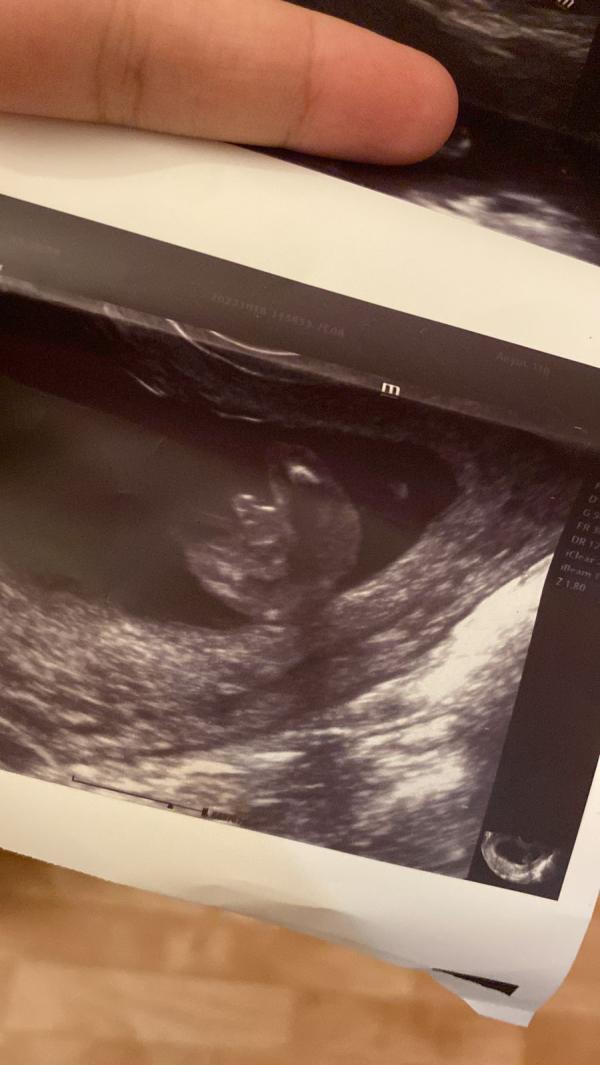

Узи. И показывают экран. Там человек. С руками. Ногами. Открывал и закрывал рот.

На учёт не становилась, просто пошла, сделала скрининг в 13-14 недель , узнали, что ждём сына(шшшок, вспоминаю слова того дедушки) и уже Приска -2 на хромосомные аномалии. Так как 1 пропустила.